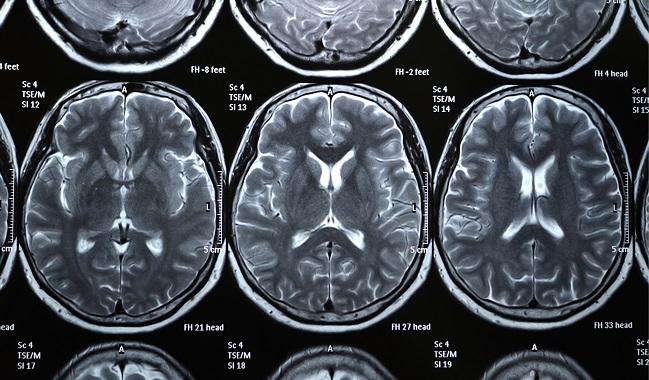

By taking an unusually thorough look at neurocognitive function, researchers have found that baseline deficits were far more common than expected among the elderly, high-risk patients of the SENTINEL trial. Diffusion-weighted MRI (DW-MRI) suggests the root cause of the difficulties—which spanned executive function and verbal and visual memory—is the burden of cerebral lesions.

Ahead of TAVR, 219 patients in the study underwent brain MRI using 3T scanners with T2 fluid attenuated inversion recovery (FLAIR) sequence. Regression modeling showed statistically significant negative correlations between preprocedural FLAIR lesion volume and baseline cognitive function; in short, the more lesions patients had, the poorer their function.

“No one’s ever been able to show that before intervention in this population there is a direct relationship between lesion volume and baseline cognition,” Lazar noted, stressing the need to use a 3T MRI scanner in future research. A less powerful 1.5T scanner may well miss lesions in the brain, he said, adding that studies using over-resolution scanners are likely to underestimate the true impact on brain integrity.